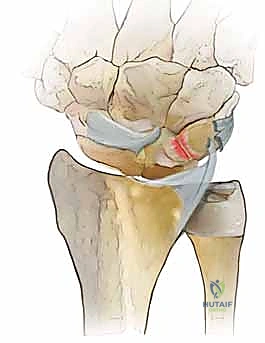

- Volar Intercalated Segment Instability (VISI): This is a more severe form of carpal collapse. While LT dissociation is a prerequisite, VISI requires additional compromise of secondary restraints, most notably the dorsal radiotriquetral ligament. Without the integrity of this extrinsic ligament, static carpal instability ensues, characterized by a volar-flexed lunate and an abnormal lunotriquetral angle. On a lateral radiograph, a normal lunotriquetral angle is approximately 14 degrees. In VISI, this angle can increase to -16 degrees or more, indicating volar flexion of the lunate.

FIG 1 • A. Intact dorsal ligaments and normal carpal alignment. Loss of integrity of these secondary restraint structures, the volar-flexed position of the lunate, and the resulting volar intercalated segment instability (VISI) carpal collapse. B. Normal anatomic alignment of the carpus as viewed from a lateral radiograph. The lunotriquetral angle is 14 degrees. C. VISI carpal collapse visible on lateral radiograph. The lunate is volar-flexed and the lunotriquetral angle is 16 degrees. D. Rupture of the lunotriquetral interosseous ligament and the dorsal secondary restraint.